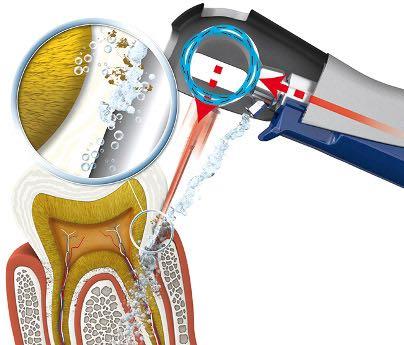

Лечение аппаратом VECTOR

В нашей стоматологии для пародонтологического лечения используется аппарат VECTOR. Высокие технологичность и мощность аппарата VECTOR позволяют справляться с самыми стойкими зубными отложениями. Новинка соответствует высочайшим стандартам профессиональной чистки зубов.

Одновременная подача полировочной суспензии Vector Fluid Polish позволяет сберечь и отполировать чувствительные поверхности. Зубной камень, микробная биоплёнка и бактерии удаляются тонкими инструментами с поверхностей корней до самого дна пародонтального кармана даже в анатомически сложных областях, не повреждая мягкие ткани.

Поверхности корней очищаются и полируются с помощью полировальной суспензии Vector Fluid Polish, содержащей частицы гидроксилапатита. Корень деликатно очищается, а не «выскабливается», как раньше . Аппарат VECTOR применяется и при профилактике пародонтальных проблем. Профилактические процедуры являются частью пародонтологического лечения. Регулярная проверка пародонтальных карманов на предмет их повторного инфицирования является важной частью поддерживающей терапии. VECTOR делает эти манипуляции абсолютно простыми и щадящими.

Применение аппарата VECTOR при лечении периимплантита : воспаление тканей вокруг имплантата является одной из основных проблем имплантологии. VECTOR наилучшим образом подходит для удаления налёта, бактерий и микробной биоплёнки с поверхности имплантатов: не повреждает в процессе обработки чувствительные материалы и супраконструкции. Так же аппарат нашёл применение при микроинвазивном препарировании Добавление абразивной суспензии Vector Fluid abrasive позволяет проводить выборочное микроинвазивное препарирование – лечение начального кариеса без бормашины. Оно проводится без воздействия высоких температур и безвредно для пульпы. При этом не ослабляются эмалевые призмы, что обеспечивает высокое качество краевого прилегания последующих реставраций.

Кроме того, движения насадки Vector носят только (гладящий поверхность корня), т.е. полирующий характер. Сам процесс разрушения прикрепления налета и зубного камня к поверхности корня происходит только за счет эффекта ультразвуковой кавитации, т.е. распространения ультразвука в водном растворе, который подается на насадку в процессе процедуры, и заполняет собой пародонтальные карманы.